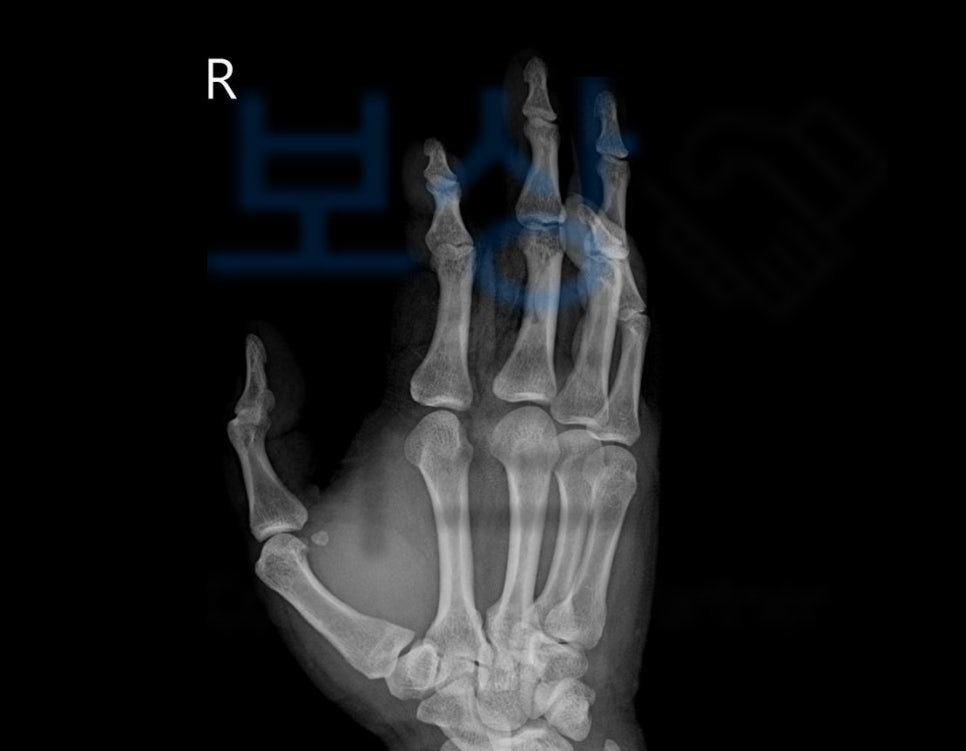

제 3,4,5수지 천수지굴건 및 심수지굴건 파열

힘줄 파열로 수술을 받았지만 위와 같이 손가락이 굽어 펴지지 않게 되었죠. 이와 같은 모습은

말렛핑거 (mallet finger)

즉 마치 손가락의 모양이 망치처럼 굽혀진 모양을 가리킵니다. 당신의 보험증권에서 “후유장해” 항목 찾아보세요. 보험증권을 보시면